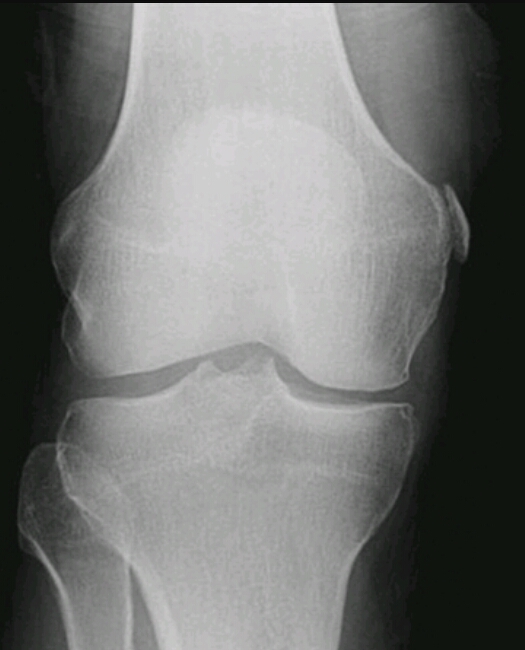

Name the disease. Name the signs of it.

DJD of the medial compartment of the knee.

Asymmetric joint space/articular deformity and irregularity

Subchondral sclerosis

Subchondral cysts

Hypertrophy of intercondylar spines

Enthesopathoc changes of non articular surface of patella